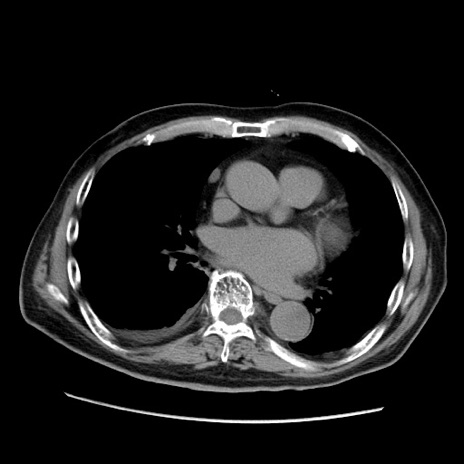

症例21(横断像)

【症例】70歳代男性

【主訴】腹痛

【現病歴】肝硬変・肝細胞癌にてかかりつけの方。約9時間前に食後より腹痛出現。症状が徐々に増悪し、嘔吐出現したため来院。

【既往歴】肝硬変、肝細胞癌(RFA、TACE後)

【身体所見】意識清明、表情苦悶様、BT 36℃、BP 129/78mmHg、P 88bpm、SpO2 97%(RA)、右上腹部から心窩部にかけて圧痛あり、反跳痛なし、筋性防御あり。

【データ】WBC 5800、CRP 0.16